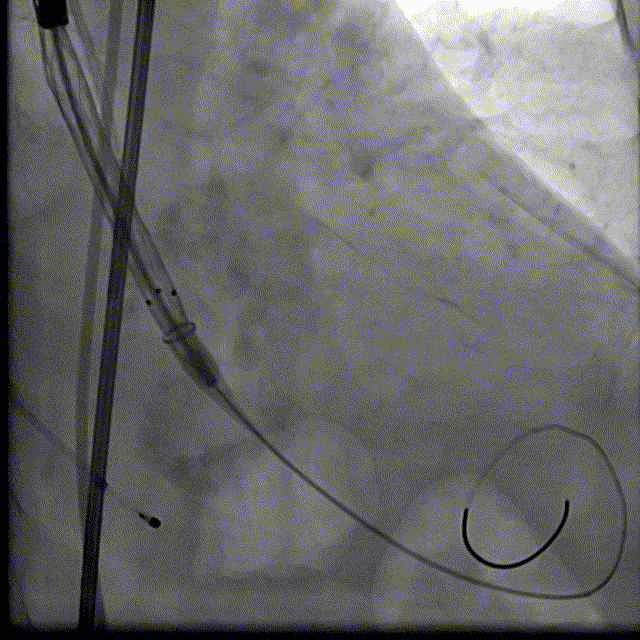

根部解刨:

手术过程